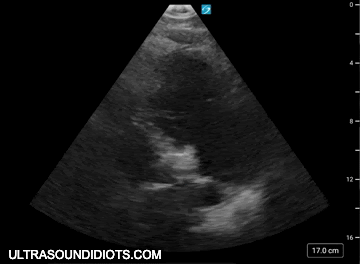

parasternal long axis - standard view